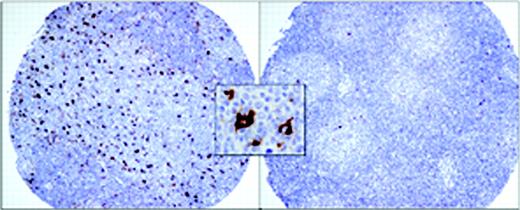

Representative tissue microarray cores of patients with follicular lymphoma. The image on the left shows the uncommon finding of large numbers of macrophages both within and surrounding neoplastic follicles (n = 12). The image on the right shows the more common finding of very few macrophages (n = 87). The insert shows the typical strong cytoplasmic staining of reactive macrophages with anti-CD68 antibody. Images were acquired using a Nikon Eclipse E600 clinical microscope and Dxm1200 digital camera and software (Nikon, Tokyo, Japan). Original magnification × 100 (objective, 10 ×/0.3 NA) for the larger panels and × 1000 (objective, 100 ×/1.3 NA) for the insert.

CD68+ macrophages were first evaluated for their consistency between duplicate cores and then qualitatively. The initial analysis of CD68 staining revealed that macrophage content could be divided into 2 groups, cases with either none or few cells positive versus many positive cells. To make the determination of macrophage numbers more objective, we counted cells using high-power magnification (× 1000 oil lens). This high magnification was used to avoid counting neutrophils and intercellular debris occasionally stained with this antibody. Five representative fields per case were counted. We chose to count in areas where the staining was the strongest and most uniform. In virtually all of the cases scoring was made easier by the fact that cases were either clearly positive or negative (Figure 1). Neither FDCs nor neoplastic B cells stained with anti-CD68 in any case.